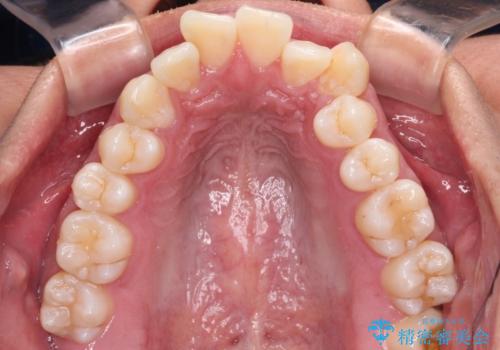

- 八重歯と飛び出している前歯を気にして来院された患者様です。

歯列としてはインビザラインでもワイヤー矯正でも対応できるものでしたが、上顎の八重歯や下顎小臼歯の捻転といったインビザラインでは時間のかかってしまう歯列不正が認められたため、補助装置やワイヤー矯正を治療当初に使用することで、インビザラインによる治療をスムーズに行えるように計画しました。